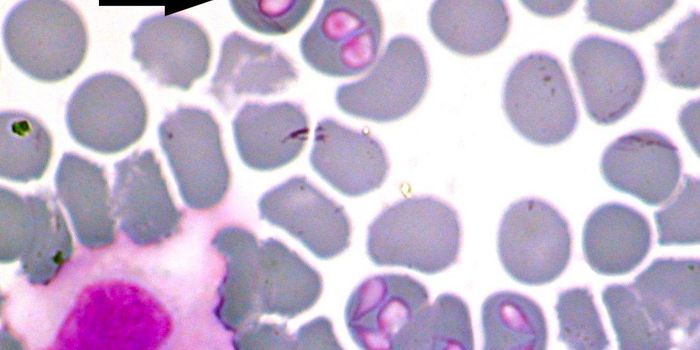

MAR 17, 2017Health & MedicineThe first human case of babesiosis was reported in 1957; until then it was thought of as a disease plaguing domes ...